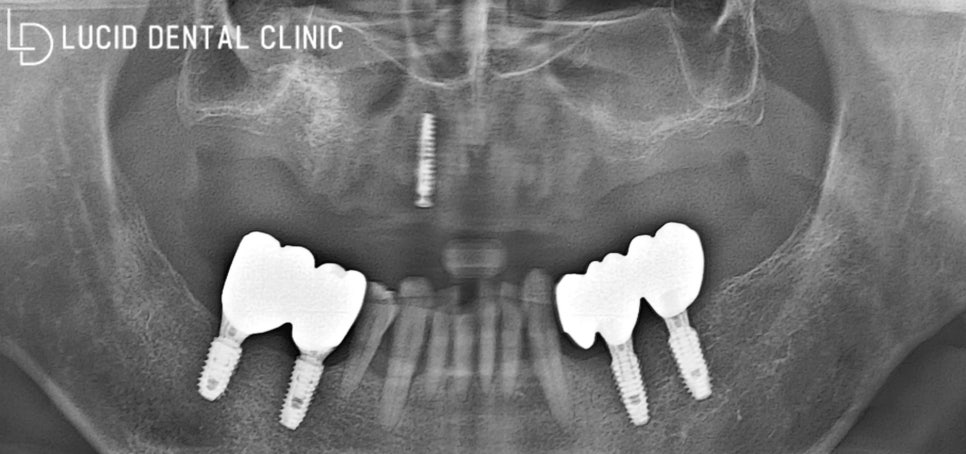

우선 이 전에 심어져 있던

픽스처부터 제거했는데요.

기존 보철을 제거하자마자

새로운 픽스처를 식립하기 위해

상악동 골 이식을 진행하였습니다.

측방 접근법 / 치조정 접근법

이 수술은 이식할 골의

양이 적으면 치조정 접근법,

많으면 측방 접근법으로

나눠서 시행하고 있는데요.

이번 환자의 경우 이식할 골의 양이 적어

치조정 접근법으로 진행하게 되었습니다.

곧바로 치은을 최소한으로 절개하고

상악동에 조심스럽게 접근하였는데요.

그 후, 상악동을 들어 올려

골 이식을 충분히 진행하고

제작한 가이드를 이용하여

즉시 식립을 마쳤습니다.

현재 환자께선 아직 회복 중이라

보철을 올리지 않은 상태인데요.

조금 더 시간이 지나고,

온전히 회복된 모습을 보이면

최종 보철을 위에 올려

마무리할 예정입니다.